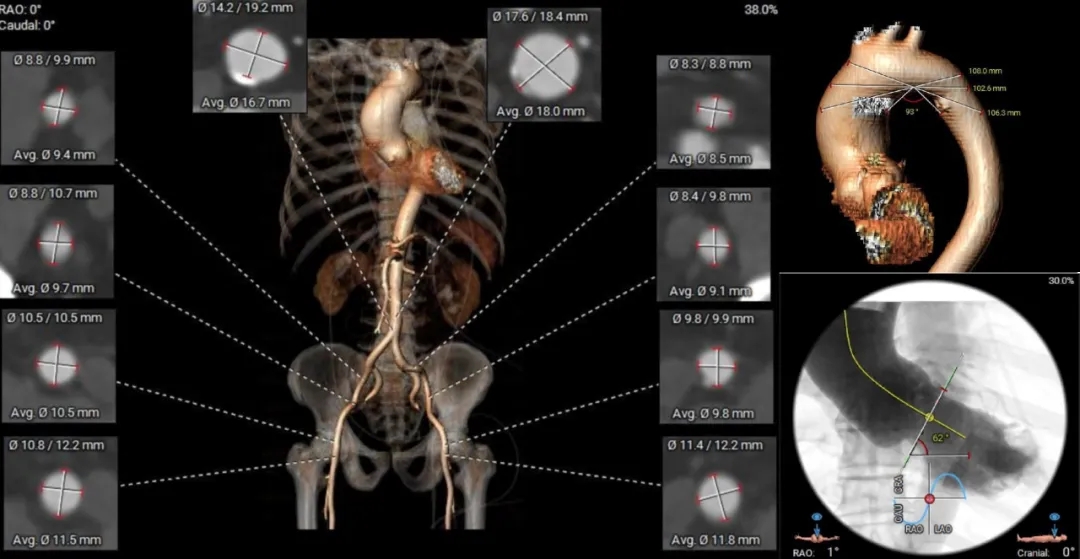

术前CT分析

主动脉根部测量

瓣上结构测量

瓣上 2mm

29.9mm

瓣上 4mm

30.2mm

瓣上 6mm

瓣上 8mm

29.5mm

冠脉风险评估

Left Coronary

19.5mm

LCA & Leaflet

13.8mm<21.9mm

Right Coronary

18.3mm

RCA & Leaflet

17.7mm<19.7mm

左、右冠脉高度可

左右冠脉异窦

左、右冠瓣叶长度<冠脉开口下缘到窦底距离

结合SOV、STJ冠脉风险可控

外周入路评估

外周无明显迂曲、钙化;血管内径可

62°横位心